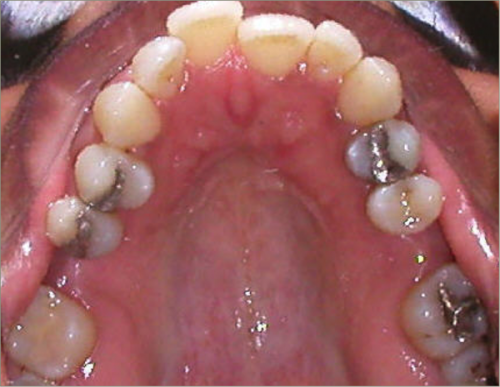

32 year old female:

Diagnosis:

- Previously lost upper first molars

- Severe lower arch crowding

- Midline discrepancy

- Narrow upper arch form

Treatment:

- Extraction of lower right first bicuspid

- Substitution of upper second molars for first molars

- Full fixed appliances

- 23 months